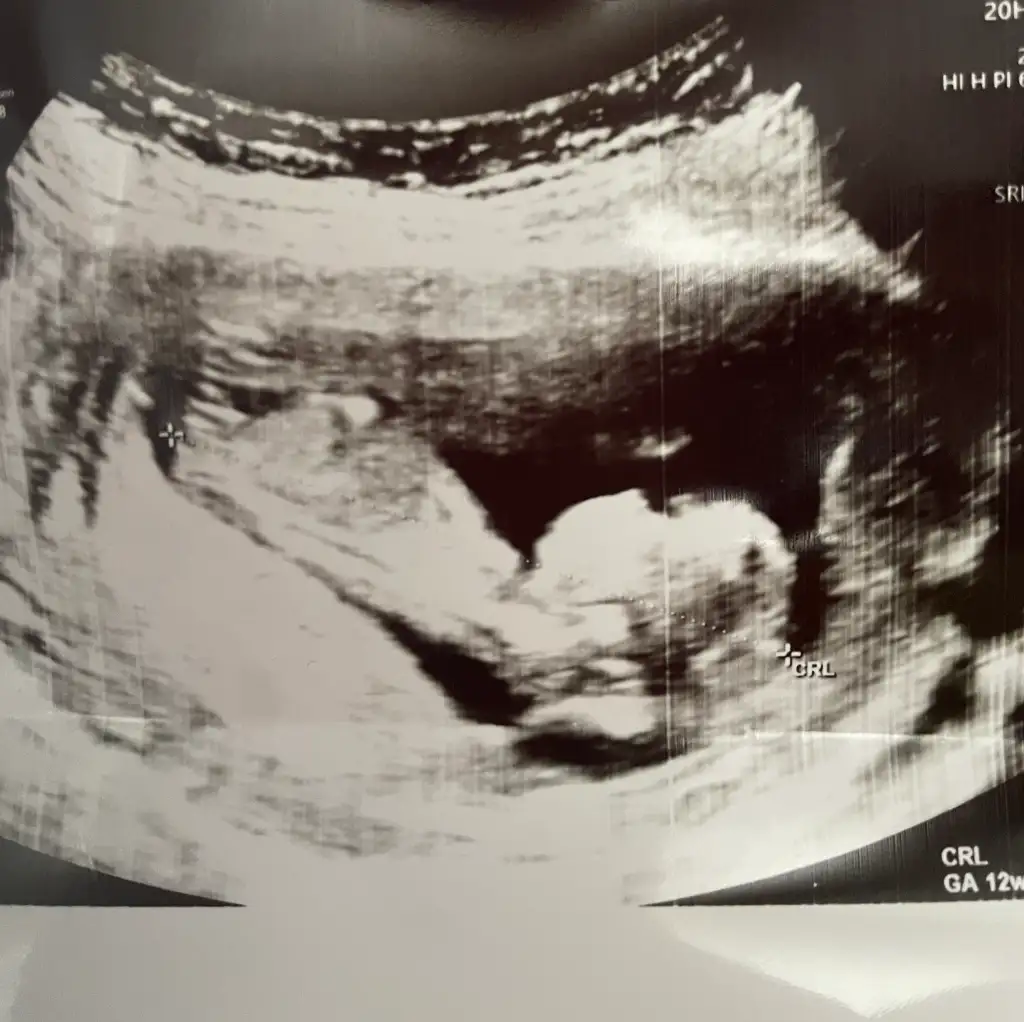

kızKızlar bana da bakar mısınız?? 13 haftalık

6 haftalık vajinal ultrason görüntüsü bize de bakabilir misiniz lütfen teyzeleri, teşekkür ediyorum şimdidenKızlar bebişlerinizin ultrason resimlerini ve cinsiyetini kaçıncı haftada olduklarını yazında kendi ultrason resimlerimizle kıyaslayıp fikirde bulunalım. Nub teorisi, kafa şekli, kemik yapısından cinsiyet teorileri tutuyor mu bakalım bir

6 haftalık vajinal ultrason görüntüsü bize de bakabilir misiniz lütfen teyzeleri, teşekkür ediyorum şimdidençok küçük ama kese kız gibi

6 haftalık vajinal ultrason görüntüsü bize de bakabilir misiniz lütfen, teşekkür ediyorum şimdidenKız gibi erkeğin kesesi genelde fasulyeye benziyo

6 haftalık vajinal ultrason görüntüsü bize de bakabilir misiniz lütfen, teşekkür ediyorum şimdidenkız gibi